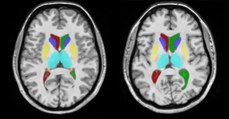

En France, 500 barrages de plus de 15 m de haut sont installés sur les cours d'eau. Il est important de pouvoir estimer l'impact écologique de ces aménagements. Le logiciel EVHA développé par Irstea permet de déterminer les débits qui respectent la vie du poisson lors des aménagements de la rivière.